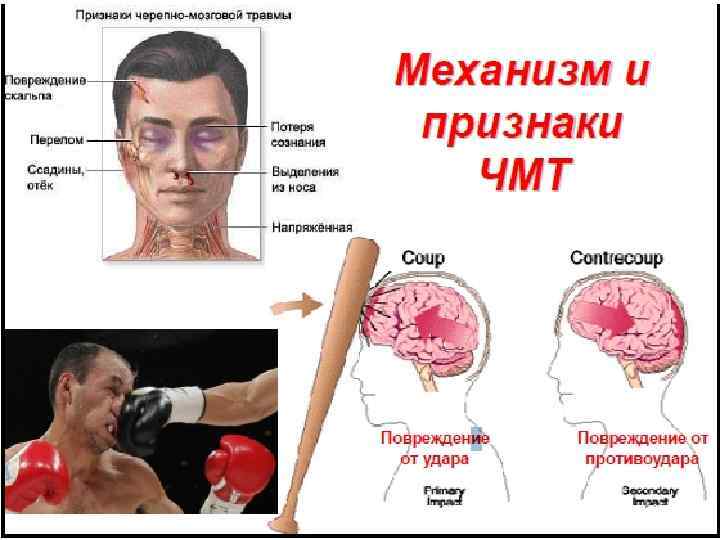

Бассүйек-ми жарақаты (БМЖ)- бұл құрамына бассүйек терісінің, бұлшық еттің, сүйектің, мидың, қантамырларының, ми қарыншақтары мен бассүйек – ми нервтерінің механикалық зақымданулары және сіңір тартылуы кіретін ұғым. Мидың жарақаттық зақымданулары жалпы жарақаттардың 25 -30%-ын құрайды, оның 2/3 өліммен аяқталады.

Бассүйек-ми жарақатының жабық және ашық түрлері болады. Жабық түріне бастың тері қабатының бұзылмаған зақымдануы жатады. Ашық түріне бассүйектің, оның негізінің зақымданып сынуы, қан және ми сұйықтығының ағуымен жүретін зақымданулар тән.